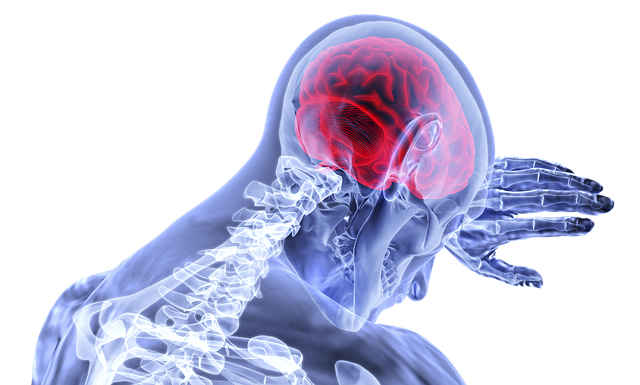

| The WHO South-East Asia Region is committed to strengthening health care services to prevent, treat and manage stroke, and to provide quality rehabilitative care for stroke-related disability. Globally, stroke is the second leading cause of death and the third leading cause of disability. One in four people are in danger of stroke in their lifetime. Lifestyle risk factors for stroke include being overweight or obese, physical inactivity, tobacco use and alcohol abuse. Medical risk factors include high blood pressure, high cholesterol, diabetes and a personal or family history of stroke or heart attack. An estimated 70% of strokes occur in low- and middle-income countries, which also account for 87% of stroke-related deaths and disability-adjusted life years. To help address this inequity, WHO continues to support all countries of the Region to identify and apply “best buy” interventions that reduce the risk of stroke, and which strengthen access for all to quality stroke services. The Region has in recent years achieved significant progress on its Flagship Priorities on preventing and controlling noncommunicable diseases (NCDs) and achieving universal health coverage, both of which are critical to Region-wide efforts to prevent, treat and manage stroke, and to increase access to rehabilitative care. All countries of the Region continue to implement multi-sectoral NCD action plans, while also expanding the provision of NCD services at the primary level, in line with the 2016 Colombo Declaration. Several countries continue to lead globally on tobacco control efforts, with India, Nepal, Maldives Thailand and Timor-Leste among the world’s top 10 countries with the largest graphic warnings on tobacco packaging. Amid the pandemic response, the Region continues to promote healthy lifestyles, including by facilitating physical activity and healthy eating, and by tackling harmful use of alcohol and substance abuse. Increased taxation of unhealthy products will not only change unhealthy behaviours, but could also enhance budgetary allocations on health, including on services to prevent, detect, treat and manage stroke and other NCDs. By the end of this year, the Region will have completed the second year of its multi-country support for stroke care improvement initiative. The programme aims to support countries to strengthen stroke management and referrals through the development and training of multidisciplinary teams consisting of doctors, nurses and rehabilitation therapists. During the first year of implementation, which started in April 2021, Bhutan, Maldives, Myanmar and Timor-Leste participated in the care improvement programme, which has since been expanded to Nepal and Sri Lanka. In all countries of the Region, several interventions can be applied to achieve immediate progress in strengthening stroke care services. First, integrating stroke prevention and detection into preventive and promotive health interventions, especially at the primary level. Community intervention, e-health and appropriate medication and lifestyle modification can prevent at least 50% of stroke events. Alongside increased public literacy in the FAST method (Facial drooping, Arm weakness, Speech difficulty and Timely emergency service) they can significantly reduce the incidence and impact of stroke. Second, strengthening existing pathways of care from the primary level up, and through to rehabilitation, ensuring that gaps are identified and addressed using a hub and spoke model. Specific focus is needed to improve fast-track referrals and enhance emergency stroke services. Third, making essential stroke medicines accessible to all. Thrombolytic medicines and other medicines for stroke are now included in WHO’s Essential Medicines List and should be integrated into national lists. Fourth, identifying and implementing high-impact innovations. Virtual capacity building in particular holds great promise, alongside tele-networking within and between countries to improve skills and share knowledge and resources. Every opportunity must be grasped. Stroke is a leading source of disability and a major contributor to lost disability-adjusted life years, especially in low- and middle-income countries. It is a needless impediment to sustainable social and economic growth. Amid the ongoing COVID-19 response, countries of the Region must leverage every chance possible to improve health and well-being, increase health system efficiency, and promote social and economic empowerment and growth. On World Stroke Day, WHO reiterates its commitment to support countries of the Region to strengthen stroke care services to reduce incidence, enhance detection, improve treatment, and increase access to quality rehabilitative services. A fairer, healthier more sustainable Region is ours to achieve. |